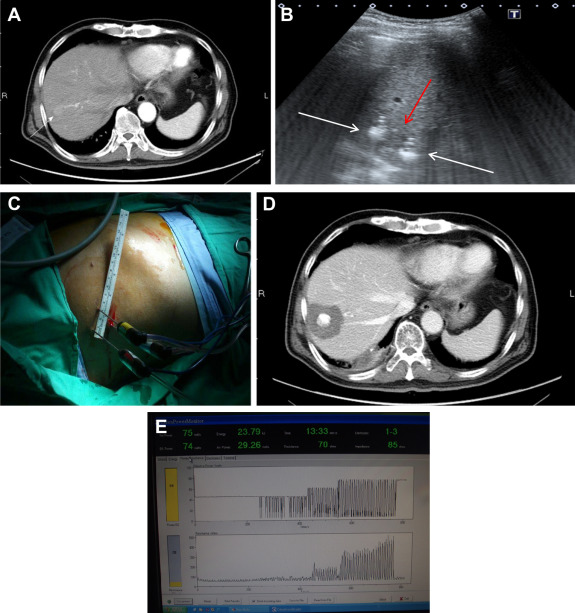

Photographs of the non-touch technique and track ablation are presented in Figure 1 ; Figure 2 , respectively.

Figure 1. (A) One 2 cm HCC in the S7. (B) Three electrodes (white arrows) were deployed around the tumor (red arrow). The third electrode was not shown in this plane. (C) The deployment of three electrodes to encircle the tumor. (D) CT of liver, 6 months after ablation, showed complete ablation with 1 cm safety margin. (E) Ladder-like appearance of the resistance profile on monitor of energy generator indicating completion of ablation. |